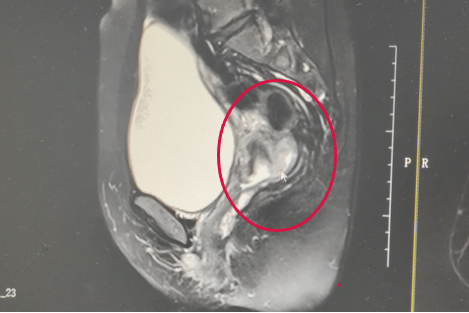

阿宝术前影像诊断

阿宝的宫颈肿瘤呈菜花样,伴有阴道出血。影像结果提示肿瘤位于宫颈后壁,考虑有宫颈癌的可能。最终,活检结果提示为中-低分化鳞状细胞癌。秉着对复大、对李红梅副主任的信任,2023年7月,阿宝接受了腹式广泛性全子宫切除术和盆腔淋巴结清扫术。术后病理为(子宫颈)低分化鳞状细胞癌,IB2期。根据术后病理结果,阿宝又补充了2个疗程的辅助化疗。经过针对性治疗,阿宝多次复查结果都显示其恢复良好,未见肿瘤病变。